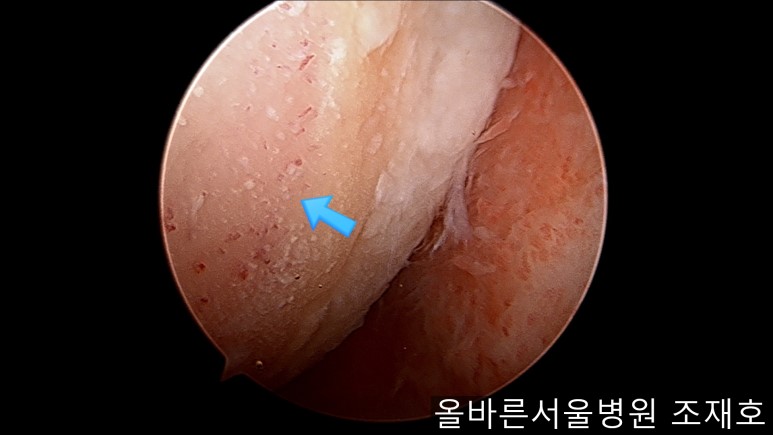

通过关节镜图像可看到:由于内侧股骨髁软骨损伤骨头已经显露出来。

胫骨上端的软骨损伤严重,也露出了骨头。

正是缺失软骨的部位碰到一起,引发剧烈疼痛,腿部逐渐变形。